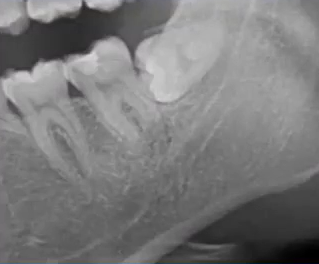

主要诊断:牙体——47龋坏伴根尖炎

牙列——35、45牙缺失,乳牙滞留,38、48智齿埋伏阻生

根尖片进一步诊断

47龋坏伴根尖炎

37继发龋!根尖炎?

25远中邻面浅龋